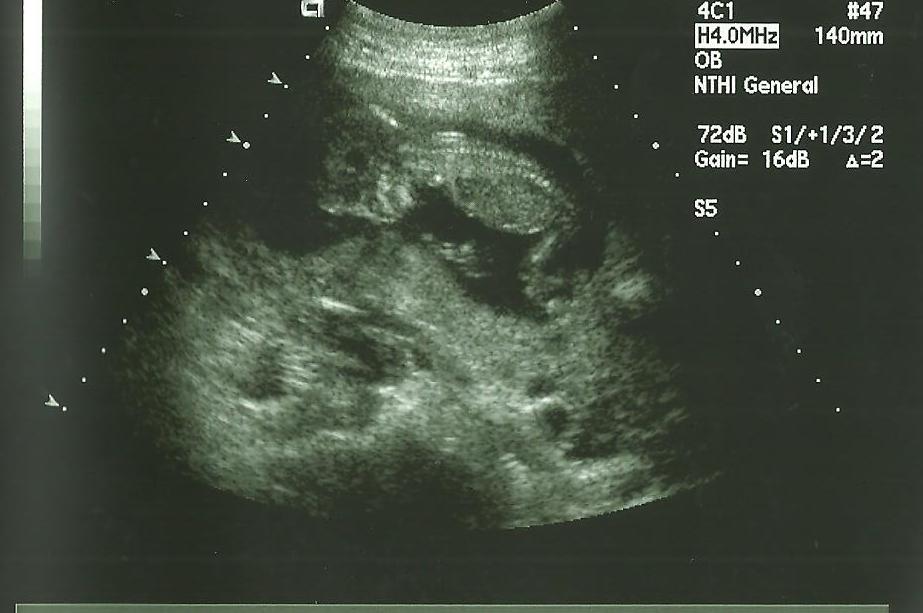

ultrasound pic at 14 weeks- what do you think?